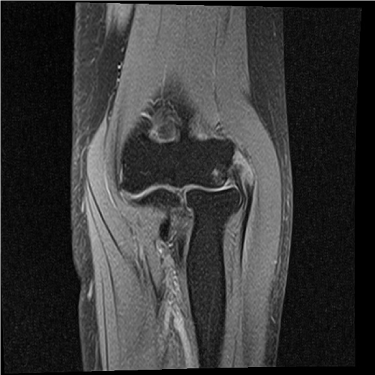

골프엘보 치료 전 MRI

2022.11.16

골프엘보 치료 후 MRI

2022.10.18

테니스엘보 치료 전 MRI

2023.02.17

테니스엘보 치료 후 MRI